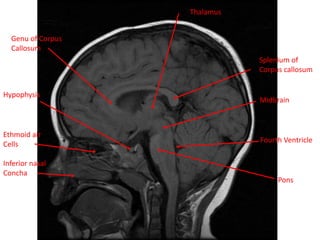

Pons

Ethmoid air

Cells

Inferior nasal

Concha

Midbrain

Fourth Ventricle

Genu of Corpus

Callosum

Hypophysis

Thalamus

Splenium of

Corpus

callosumGenu of corpus